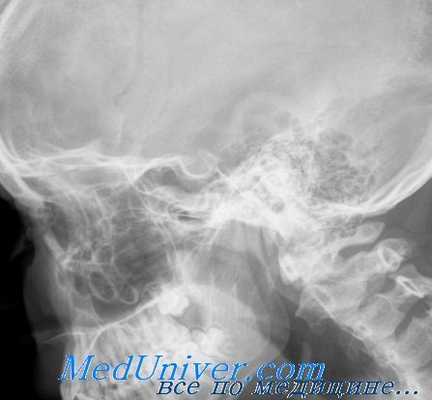

Диагностика опухолей орбиты — один из наиболее трудных разделов офтальмологии. Методами исследования являются рентгенография, при которой можно отметить истончение или разрушение стенок, увеличение размеров и затемнение пораженной орбиты, компьютерная томография, показывающая наличие опухоли, локализацию и протяженность, орбитография, основанная на рентгенологическом контрастировании орбиты, венография, термография орбиты, каротидная ангиография, В-метод эхографии (сканирование). При сосудистых поражениях орбиты и подозрении на злокачественную опухоль противопоказан метод орбитографии. Для определения злокачественности новообразования применяют радионуклеидное исследование с радиоактивным фосфором — 32 Р, йодом — 125 J и 131 J, стронцием — 85 Sr и др. Однако метод не точен, т.к. некоторые доброкачественные новообразования и псевдоопухоли орбиты могут накапливать изотоп, подобно злокачественным новообразованиям.

При рентгеновском исследовании в первый период развития новообразования отмечается затемнение пораженной глазницы, затем увеличение ее размеров, истончение ее стенок, узуры, иногда гиперостоз кости. Наличие в области глазницы тромбированных сосудов помогает диагнозу. Наиболее точный диагноз помогает поставить компьютерная томография с контрастированием, а также ультразвуковое сканирование.

Течение остеомы может осложниться эмпиемой придаточной пазухи с последующим развитием субпериостального абсцесса, абсцесса мозга, менингита. Остеомы могут прорастать из пазух не только в орбиту, но и в интракраниальную полость. Решающим в диагностике является рентгеновское исследование. На рентгенограммах определяется четкая тень, по интенсивности напоминающая костную ткань. Размеры остеом разные — от малых, величиной с горошину, где лучше применение компьютерной томографии, до огромных, занимающих соответствующую пазуху и полость глазницы.

Таким образом, все изложенное выше с несомненностью указывает на то, что на основании одних только клинических признаков нельзя с полной уверенностью решить вопрос о наличии опухоли глазницы и тем более о тех изменениях, которые происходят в полости глазницы в связи с ростом опухоли. Здесь-то значительную помощь клиницисту может оказать рентгенологический метод исследования. С помощью такого исследования в ряде случаев удается не только уточнить диагноз и выяснить причину экзофталма, но также определить характер и структуру опухоли. Такой метод исследования позволяет также с большой точностью установить место исхода опухоли, направление ее роста и наличие прорастания в смежную область.

Обследование больных с опухолью глазницы. Крайне полезно провести рентгенографическое и томографическое обследование глазницы, в результате которого можно будет сделать заключение о состоянии глазницы и зрительного канала.

При проведении КТ это заключение может быть детализировано, поскольку будет получена информация о локализации, размере и степени распространения опухоли в пределах (и вне пределов) глазницы. При этом также получают сведения о степени эрозии кости и поражения мягких тканей. Ультразвуковые исследования могут помочь быстро обнаружить опухоль. По возможности следует проводить биопсию, однако она сопряжена с риском диссеминации опухоли, возникновения геморрагии и развития слепоты. При наличии инкапсулированной опухоли ее лучше всего удалить.